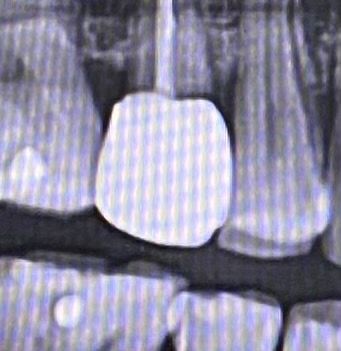

치아와 크라운 사이 검은줄 들뜬건가요??

치아와 크라운사이 검은줄 무엇인가요??

크라운 1년정도 사용 했어요

• 2번 째 사진

x-ray가 투사 되면서 사란된 흔적입니다. x-ray가 크라운에 산란되면 크라운 주위는 검게 보이게 됩니다. 일반적인 경우에는 틈이지만 크라운 주위에는 지금과 같은 산란 음영이 자주 나타난다고 보시면 됩니다. 또한 촬영 각도에 의해 이러한 것들이 조금 더 부각되어 보일 수 있습니다.

치아와 크라운을 붙이는 시멘트가 있는데, 그 시멘트가 결손된 부위로 인한 시맨트갭이 방사선사진상에서 나타난 것 같습니다. 치아에 크게 통증 없으면 더 쓰셔도 되고, 나중에 크라운 떨어지면 치과 가보세요. 우려하시는 이차충치는 아닌 것 같습니다.